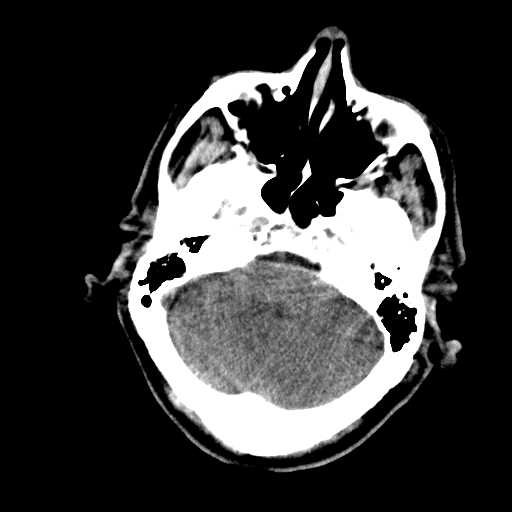

Figure 2: Examples of CT scan slices that were removed during preprocessing. These slices were eliminated because of lack of relevant brain tissue, or poor image quality, ensuring that only the most informative slices contribute to the classification process.

Slices from CT scan images that lacked relevant diagnostic information were manually removed, as illustrated in Fig. 2. This process excluded slices with missing brain tissue or poor image quality, ensuring that only the most informative and clinically relevant scans were used for classification. Following this initial filtering step, additional preprocessing was applied to further refine the dataset.